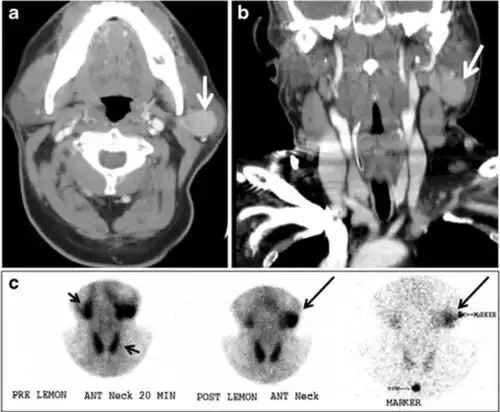

Fig. 18. Lingular thyroid in a 33-year-old male who presented with oropharyngeal bleeding. an Axial enhanced neck CT scan at the level of mandible demonstrates a 3 × 3 × 3.4 cm round, partly well-delineated, heterogeneously enhancing lesion (white arrow). It is predominantly on the left side of the oropharynx and to some extent at the mid part of the base of the tongue. The thyroid gland was normal (not shown). b Image of the anterior face and neck taken 20 minutes after Tc99m-Pertechnetate injection shows absent thyroid radiotracer uptake in normal thyroid anatomical location (black short arrows). There is an area of increased uptake (long black arrows) corresponding to the posterior tongue mass identified on CT scan.[1]